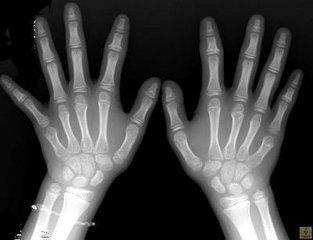

(图:罗先生双手、双足关节痛风石明显)

查体:双手指关节鹌鹑蛋大小痛风石、左膝关节胡豆大小痛风石、双手指鸡蛋大小痛风石、双足跖趾关节胡豆大小痛风石、左足后跟胡豆大小痛风石,关节活动受限,肾功能不全。

实验室检查:血清尿酸635umol/L,血肌酐157.2umol/L,甘油三脂252mg/dL,血沉30mm/h.C-反应蛋白44.40mg/L。

(图:罗先生治疗后的手部X光)

治疗一个疗程后,罗先生的病情初步得到缓解,双手指关节僵硬感缓解,肿痛现象有所消退,多关节细小痛风石基本溶解。

治疗二个疗程后,罗先生的多关节肿僵现象逐渐好转,痛风石也清除了许多,肾功能恢复正常,关节活动度提高。为了巩固加强疗效,陈建春主任还未罗祖云进行了食疗调理辅助治疗,达到内外平衡、巩固临床治疗效果的目的。

三个疗程的治疗结束后,罗先生来院复查,数据显示各项指标均达正常范围,陈建春主任表示已达临床康复标准。离院前,陈主任还嘱咐罗先生,回去要注意保暖,饮食要均衡,多多休息,做些有氧运动,帮助身体恢复到较佳状态。